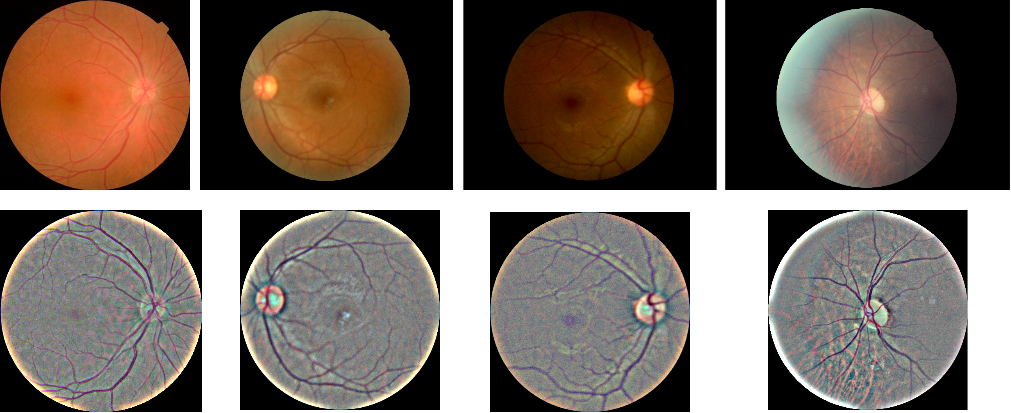

To enhance the uniformity of retinal images for our model’s categorization task, we performed the following pre-processing steps: i) Removal of black regions: Images with noticeable black areas around the eyes, caused by differing aspect ratios, were trimmed as they contained irrelevant data. We converted the images to greyscale and identified black areas based on pixel intensity, removing vertical and horizontal black rectangles. ii) Resizing: All images were resized to a standard dimension of 224 x 224 pixels after eliminating black regions. iii) Standardization of eye shape: Circular cropping around the center of each image was applied to achieve a consistent eye shape representation. iv) Smoothing: A Gaussian filter was used to reduce lighting and brightness variations in the pre-processed images. The results of this set of pre-processing steps are depicted in Fig 1.

Refer to caption

Figure 1: Pre-processing of DR images to uniform shape, size, and illumination. Here, Top(input), Bottom(output)